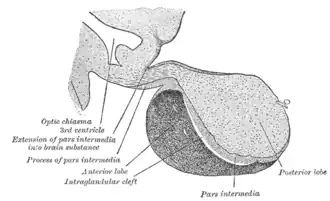

Do ponto de vista fisiológico, a hipófise é dividida anatomicamente e funcionalmente em duas partes distintas: o lobo anterior (adeno-hipófise) e o lobo posterior (neuro-hipófise). A adeno-hipófise possui origem de células epiteliais, enquanto neuro - hipófise possui origem nervosa. Entre essas duas porções existe uma zona pouco vascularizada chamada de parte intermédia, praticamente ausente em humanos, mas bem desenvolvida e funcional em outros animais.[2]

Embriologia: durante o processo de formação na vida embrionária, observa-se que a parte distal e a parte intermediaria se originam da bolsa de Rathke (originada do teto da cavidade oral do embrião, ectoderma, o estomodeu) e que a parte nervosa se origina de uma invaginação do assoalho do terceiro ventrículo. Em seguida, as duas partes se aproximam e formam uma glândula aparentemente única.[1] Como remanescente deste desenvolvimento embriológico, observamos a presença de folículos entre neurohipófise e adenohipófise, cuja função é ainda desconhecida.

Histologia: Limite da neuro-hipófise com a adeno-hipófise

Em fotomicrografia com menor aumento, se observa uma porção da pars distalis, uma porção da pars nervosa da neuro-hipófise e entre essas duas situa-se a pars intermedia da adeno-hipófise.

A pars intermedia é, pelo menos parcialmente, uma glândula endócrina folicular. Pequenos folículos glandulares estão presentes.

A pars nervosa corresponde à neuro-hipófise. É formada por fibras nervosas provenientes do hipotálamo, pituícitos (células da neuroglia) e por capilares sanguíneos. Não há corpos de neurônios na pars nervosa. A maioria dos núcleos observados nesta porção da glândula pertence a pituícitos.